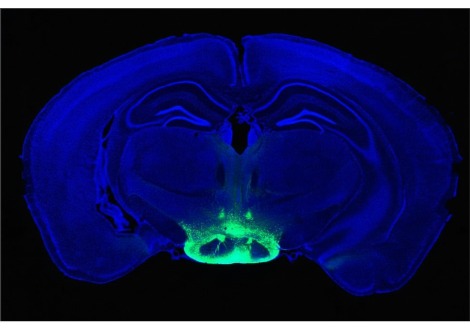

لاحظت سوثانا وزملاؤها مرضى الصرع الذين زُرعت بأدمغتهم جراحيًا في وقت سابق بأقطاب كهربائية للسيطرة على نوباتهم. كانت الأقطاب الكهربائية موجودة في الفص الصدغي الإنسي ، وهو مركز الدماغ المرتبط بالذاكرة ويشتبه في أنه ينظم التنقل ، مثل جهاز GPS.

قال المؤلف الأول ماتياس ستانجل ، باحث ما بعد الدكتوراه في مختبر سوثانا: "أظهرت الدراسات السابقة أن موجات الدماغ منخفضة التردد بواسطة الخلايا العصبية في الفص الصدغي الإنسي تساعد القوارض على تتبع مكان وجودهم أثناء تنقلهم في مكان جديد". "أردنا التحقيق في هذه الفكرة لدى الأشخاص - واختبار ما إذا كان بإمكانهم أيضًا مراقبة الآخرين بالقرب منهم - لكن التكنولوجيا الحالية أعاقتهم."